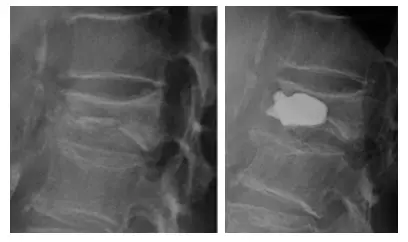

手術は椎体形成術:BKP(Balloon Kyphoplasty)と言われる方法で行うことが多いです。

BKPは骨折してしまった背骨の中で風船を膨らませ、つぶれを直し、セメントを充填して骨を固定する方法です。

手術は全身麻酔で行い、傷は約5mm程度のものが2箇所のみです。

手術時間は通常30分程度です。

- 背中を約5mm程度2箇所切開し特殊な器具を挿入します

- 特殊な器具の風船を膨らませつぶれた骨を持ち上げてできるだけ良い形に戻します

- 風船で作ったスペースにセメントを重鎮します

- セメントが固まったら終了です